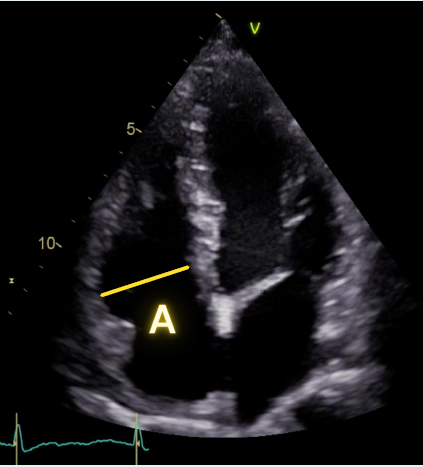

Apical 4 Chamber measurement

A: RV basal diameter in diastole (when RV is biggest)